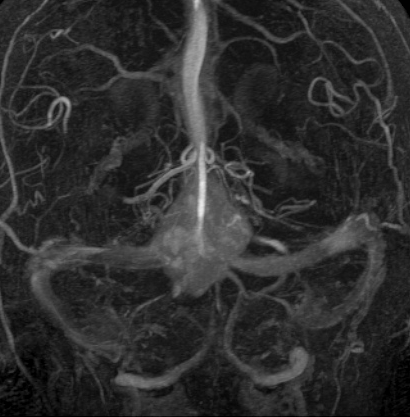

フォン・ヒッペル・リンドウ病の患者さんの脊髄(胸髄)にできた血管芽腫です。上下の脊髄が腫れたり,脊髄の中に空洞(腫瘍のう胞あるいは脊髄空洞症といいます)ができます。 手術治療は症状が出るまで,あるいは症状がかなり強くなってからしかしません。なぜなら,たくさんできる(多発)することが多くて,複数回の手術になってしまうこともあるからです。手術をするたびに,四肢のしびれや麻痺などの後遺症がのこる可能性もあるので,この手術は,脊髄腫瘍の手術経験が相当にたくさんある脳外科医にしかできません。

フォン・ヒッペル・リンドウ病 VHL の血管芽腫が大きくなるかどうか

Ammerman JM, et al.: Long-term natural history of hemangioblastomas in patients with von Hippel–Lindau disease: implications for treatment. J Neurosurg 105: 248-255, 2006 10年以上経過を見た19人のVHLの患者さんで143個の血管芽腫が追跡されました。138個で腫瘍増大しましたが症候性となったものは58個でした。特に注意しなければならないことは,血管芽腫がstuttering pattenという増大傾向をとることです。step-wise growthともいわれます。要するに,大きくなってもまた増大傾向が停止するという珍しい傾向があるということです。 平均増大期 growht period が13ヶ月で,平均静止期 quiescent period が25ヶ月と書かれています。15か月増大してその後に25ヶ月大きくならないで静止するという意味です。のう胞性血管芽腫の増大速度と症候性となる確率は高いと書かれています。また脊髄血管芽腫では22mm3以上のもので症候性となる確率が高いとの結果です。

フォンヒッペルリンドウ病に合併した大きな右小脳半球血管芽腫です。大きなものでは静脈環流障害(鬱滞)のために脳浮腫を来すことが多いし,その分,手術時の静脈圧が高くて止血が難しいと考えなければなりません。水頭症を呈して症状は重篤でしたが,右後頭窩開頭で比較的簡単に全摘出できて回復しました。小脳半球に生じるものは手術で大きな障害を残すことはほとんどなく術後の症状症状の回復も順調なことが多いです。

同じ患者さんです。上記の手術の5年後に新たな血管芽腫が激しく増大しました。これは小脳虫部なので両側の上小脳動脈がfeeding arteryとなります。bilateral occipital transtentorial approachという特殊な手術方法でしか摘出できません。幸いこの腫瘍も無事に全摘出できました。

VHLの患者さんはこうなる前にもう少し頻回に脳のMRIをして慎重に経過観察をしなければなりません。少なくとも2年に一度のMRIは必要です。逆に,stuttering patternがあり,増大傾向を示しても増大停止することがあるので,手術するかどうかの判断は頻回にMRIをして慎重にしなければなりません。VHLの患者さんはとても多数回の手術を受けるのでどうしてもしなければならない時だけ手術摘出をします。